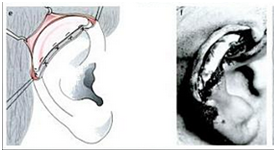

The first stage operation was implantation of the cartilage framework. The skin incised about 3-4 mm lower than the marked height of the stump.7,8 Subcutaneous pocket is developed, about 1 cm larger than the height of the superior helical margin and the post auricular stump skin is sutured to the lower margin of the incision. The framework is attached using 5.0 braided suture and inserted to the pocket. Closure of the skin wound, vacuum drainage, and mattress sutures (Figures 7-10).7

Figure 8 Developed subcutaneous pocket.7